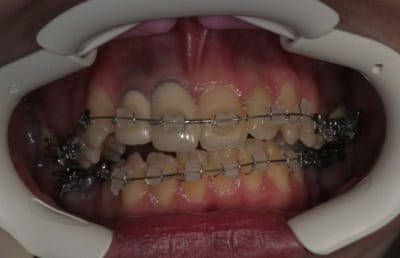

Cas présenté :

Sexe : XX

Age 24 ans

m’a été envoyé en Ortho

Motivation : voudrait arranger son sourire ( 11-21),

Début du cas :

pose mat Sup.